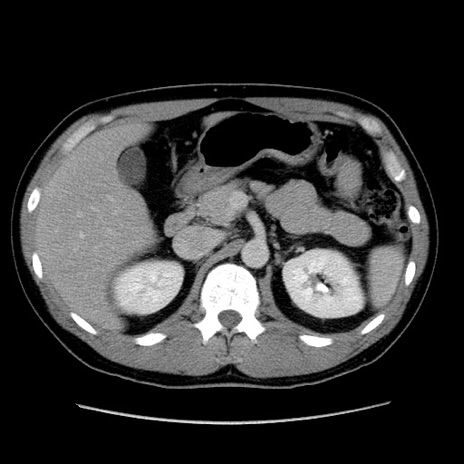

冠状断像

【症例】30歳代男性

【主訴】腹痛、嘔吐

【現病歴】昨晩から突然の腹痛あり、その後嘔吐、軟便も出現。腹痛が改善しないため救急搬送となる。2日前にしめ鯖の食事歴あり。

【身体所見】意識清明、苦悶様、BP 135/90mmHg、BT 35.7℃、腹部:平坦、やや硬、心窩部〜臍部に自発痛、圧痛あり、筋性防御+、反跳痛-

【データ】WBC 8100、CRP 0.57